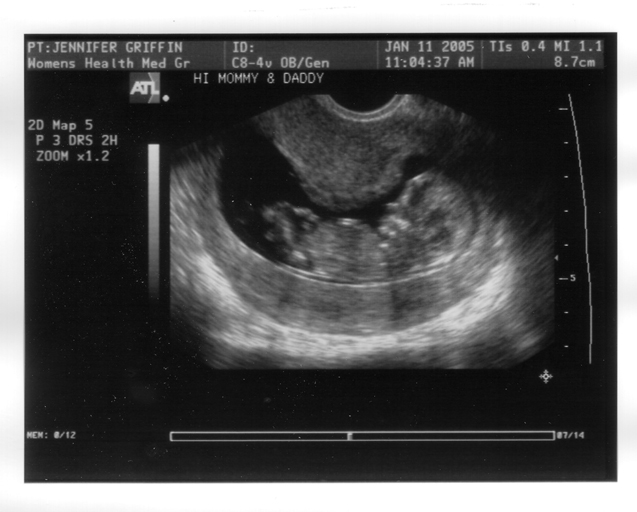

We got a good view between its legs during the scan, but the doctor said it was too early to say whether we're having a boy or girl.

We are having an alien baby!